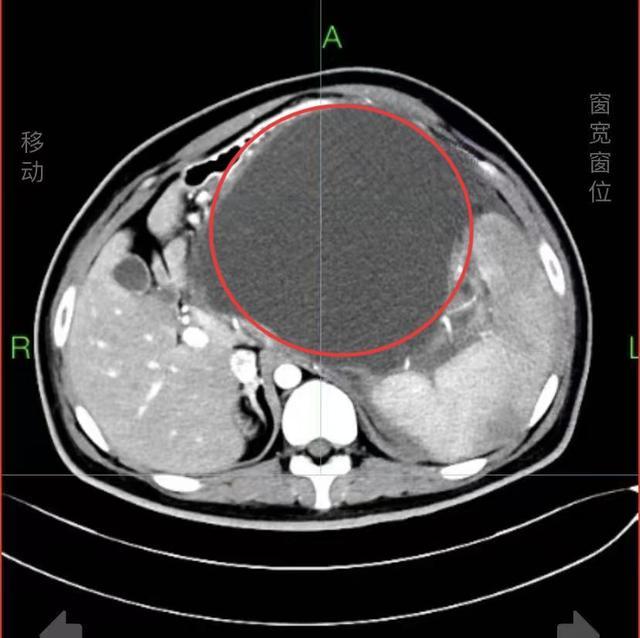

(CT影像中的巨大囊肿。)

长沙22岁的小伙子小张最近一段时间腹部逐渐隆起,仿佛怀胎数月,还伴有上腹胀痛、恶心呕吐等症状,到湖南省人民医院消化内科就诊,医生发现其腹腔内长出一个直径16厘米的巨大胰腺假性囊肿,严重压迫周边脏器,犹如一枚“定时炸弹”,十分危险。

小张三个月前因凶险的急性坏死性胰腺炎在鬼门关走了一遭,在家附近医院经救治才脱离危险。没想到胰腺炎引发胰腺体尾部假性囊肿,囊肿迅速长大,几乎占据了腹腔的“半壁江山”,不仅将胃、十二指肠等重要脏器挤压变形,更随时有破裂引发感染、大出血,小张再次面临致命风险。